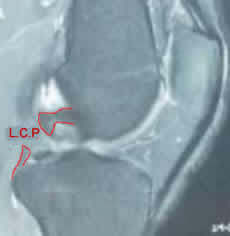

Le ligament croisé postérieur (flèche jaune sur l'irm) fait partie du pivot central du genou avec le croisé antérieur. Il stabilise le tibia sous le fémur, en empêchant le tibia de partir vers l'arrière.

Il est confirmé par l'IRM

L'IRM confirme le diagnostic, et surtout recherche les lésions associées +++, mais ne donne pas d'élément sur l'importance de la laxité.